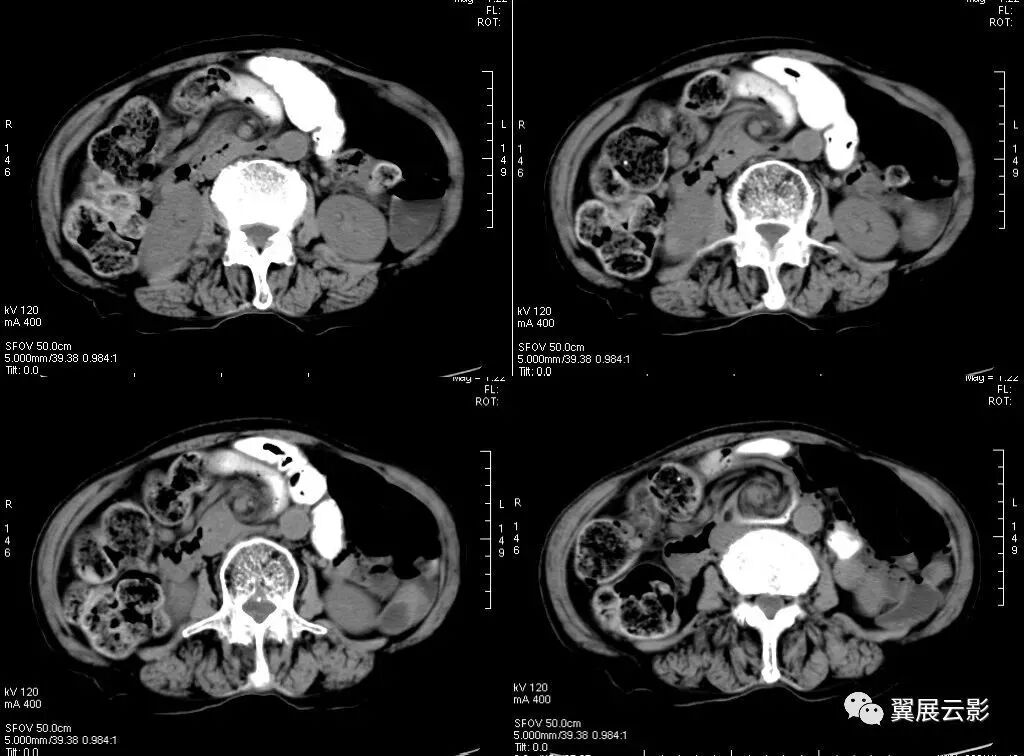

下图肠扭转病例:

在CT扫描时,多个条带状影围绕一个中心结构呈旋涡状排列,形成一软组织团块影。该征象高度提示小肠扭转时输入和输出肠管围绕一固定梗阻点旋转,并导致肠系膜绕轴旋转,是肠扭转的特异性征象,该征象包括肠管"漩涡征”及肠系膜血管“旋涡征”两个方面。当扭转小肠的输入襻和输出襻围绕着固定的梗阻点旋转时,肠系膜也随之沿旋转轴扭曲并紧密缠绕在肠襻之间,这些扭曲的肠襻和肠系膜血管分支形成了旋涡征中软组织密度的飘带状影,其背景是由肠系膜脂肪形成的低密度,由此形成了类似于气象图上旋风图样的外观,称为漩涡征。

当CT扫描与小肠的扭转轴相垂直时,漩涡征更清楚。肠扭转是一段肠袢沿其系膜长轴旋转而造成的闭袢型肠梗阻,同时肠系膜血管受压,也是绞窄性肠梗阻。常常是因为肠袢及其系膜过长,系膜根部附着处过窄或粘连收缩靠拢等解剖上的因素,并因肠内容重量骤增,肠管动力异常,以及突然改变体位等诱发因素而引起。肠扭转部分在其系膜根部,以顺时针方向旋转为多见,扭转程度轻者在360度以下,严重的可达2-3转。常见的肠扭转有部分小肠、全部小肠和乙状结肠扭转。

肠扭转时相应的肠系膜血管发生旋转,在CT图像中出现旋涡状改变通常称为“漩涡征”,表现形式有以下三种:肠管漩涡、肠系膜漩涡及以肠系膜血管为主的漩涡。因大部分病例肠系膜及系膜血管走行较复杂多不在一个平面上显示,因此肠系膜血管漩涡征以增强轴位CT 观察较好。 肠扭转后供给肠管血供的肠系膜血管发生扭曲,肠道血供障碍,肠管缺血缺氧而坏死形成绞窄性肠梗阻。因此,必须尽快准确判断患者的病情以选择哪些适合非手术治疗,哪些需要尽快手术探查。CT在判断肠梗阻患者中的作用,其敏感性达到83%,特异性为93%,准确率为91%。 小肠扭转虽然少见,但却是威胁生命的外科急症。

急腹症中的肠扭转、肠粘连、内抓疝等在很多情况下肠系膜及其血管同时发生旋转,并在CT图中显示,只要出现旋涡状改变,都可称之为漩涡征。漩涡征表现可有以下形式:肠管漩涡,肠管漩涡必有水肿系膜伴随,才能将肠管显示,多为静脉,可分为主干或分盘,前者常是扩张的肠系膜r静脉( SMV)围绕肠系膜上动脉(SMA)旋转后者系膜静脉分支构成漩涡状。Fisher所描述的CT上出现的漩涡征一个肠扭转的病例,该例涡轮的中心是肠系膜上动脉,涡轮样的外观是由环绕的扭曲肠襻所形成。Fishe提出漩涡征以后的文章中,许多作者描述了肠扭转的不同形式。Shaff等将漩涡征的定义延伸到乙状结肠扭转,此处漩涡征中的涡轮是由输入襻和输出襻所形成,中心部分由麻花状扭曲的肠管和肠系膜所构成,其指出涡轮的紧密度与肠扭转的程度成正比。Frank等提出漩涡征也可出现在自肠扭转,此处涡轮的构成包含了扭曲的肠系膜,塌陷的盲肠以及末端回肠襻。扩张的肠段在漩涡征出现处突然中止,高度提示肠扭转,且多为急性发生或者提示液体流入或分泌减少。

李文华等指出,漩涡征出现的位置有可能提供引起漩涡的病因。上腹部出现漩涡征,肠管又固定于定位置者,要考虑是否并发于内疝,如小网膜囊内疝、十二指肠旁疝等,应注意识别其解剖关系;中腹部出现漩涡征,多为单纯小肠扭转,而下腹部出现漩涡征,可能与乙状结肠扭转有关。 CT上漩涡征的出现能够提示肠扭转的发生,但是如果扫描平面与扭转轴不相垂直的话,漩涡征可能显示得不明显,其他有关小肠扭转的CT征象也有文献描述,比如扩张肠襻的放射状分布或U形结构,或者在扭转处肠管的纵切面形成的三角状或逐渐变细,上述这些CT征象在小肠闭襻性肠梗阻也可以观察到,依照闭塞段的长度、肠管扩张的程度、闭襻的位置方向以及CT扫描时切面的相对位置不同,显示也有所差异。 Blake和Mendelson报道部分手术如结肠部分切除术后患者,出现漩漏征并不具有特异性。尽管这些下术可能使肠管及肠最膜旋转述180度,但极少出现360度或更大角度旋转形成的漩转形成的漩涡征,因此在这些术后患者中出现漩涡征时,肠扭转仍然是一个排除性诊断。 总之.漩涡征的出现高度提示小肠扭转.但需要注意排除闭襻性肠梗阻。